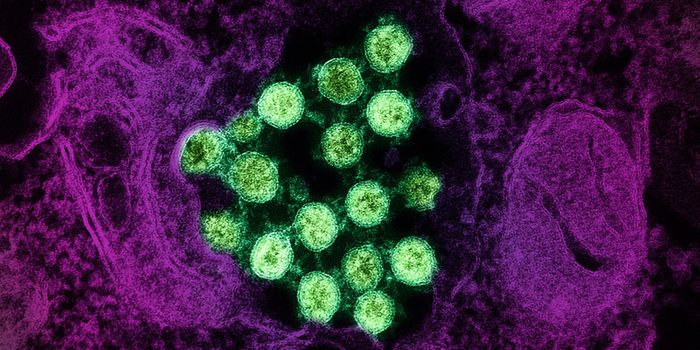

SEP 08, 2024MicrobiologySARS-CoV-2, the pandemic virus that causes COVID-19, has mutated endlessly since it burst on the scene in late 2019. An ...

AUG 27, 2024MicrobiologySince the start of the COVID-19 pandemic, the virus that causes the illness - SARS-CoV-2 - has had a practically infinit ...